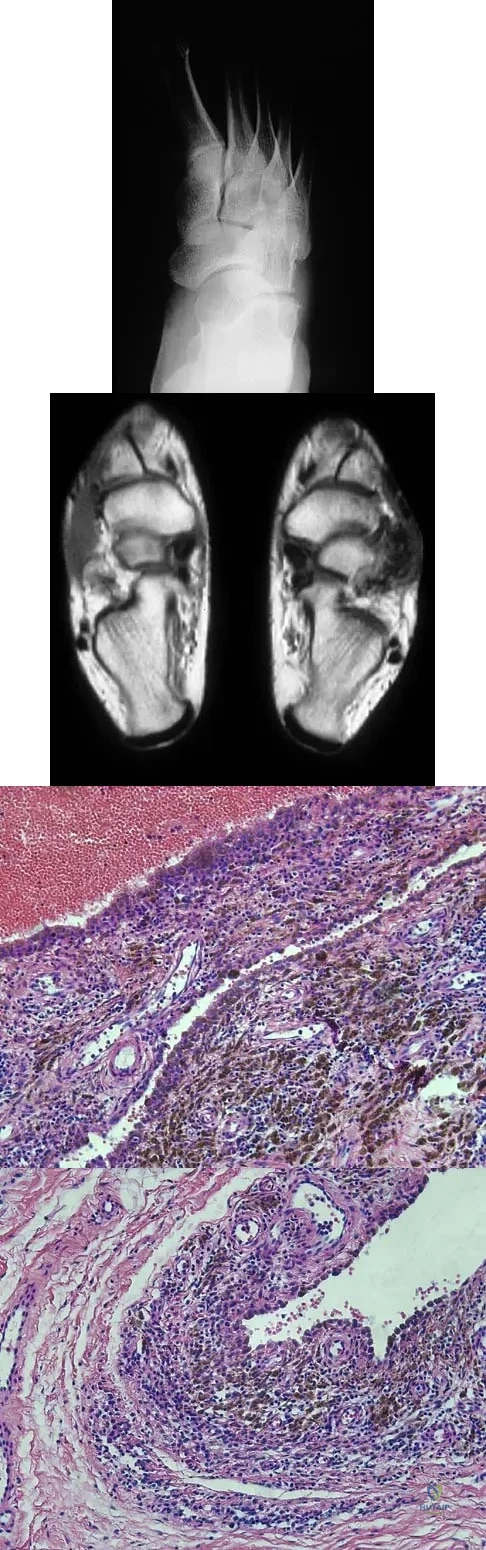

A 35-year-old man reports the development of a painful 2-cm nodule on his dorsal wrist over the past 3 years. A surgeon excised the lesion with a presumptive diagnosis of a ganglion cyst. Histology sections from the excision are shown in Figures 11a and 11b. What is the most likely diagnosis?

Explanation:

The histologic appearance of the soft-tissue lesion reveals compact nests of cells with a clear cytoplasm surrounded by a delicate border of fibrocollagenous tissue. There can be scattered multinucleated giant cells. This is consistent with a clear cell sarcoma, also called malignant melanoma of soft parts. This tumor is usually positive for S-100 and HMB45 (a melanoma-associated antigen). These tumors are frequently found around the foot and ankle. Similar to epithelioid sarcoma, it is usually intimately bound to tendons or tendon sheaths. Often the tumors are present for many years. The classic histologic appearance of this lesion differentiates it from the other choices. Enzinger FM, Weiss SW: Soft Tissue Tumors, ed 3. St Louis, MO, Mosby, 1995, p 913.